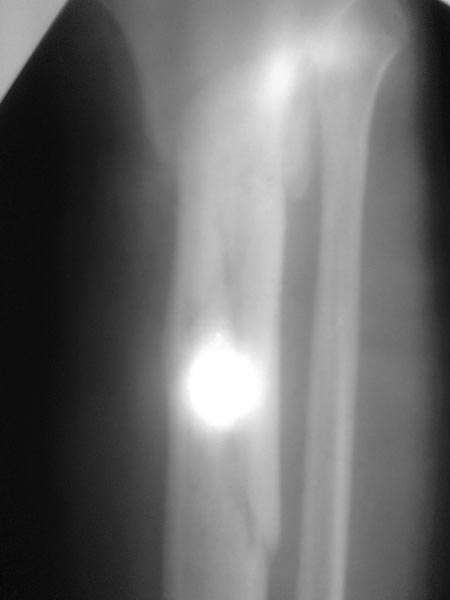

Спасибо за обсуждение.Отправил остальные R, изиняюсь за качество.

3.Перелом на 2 уровнях, есть искривление костно-мозгового канала. Проксимальный отломок короткий.